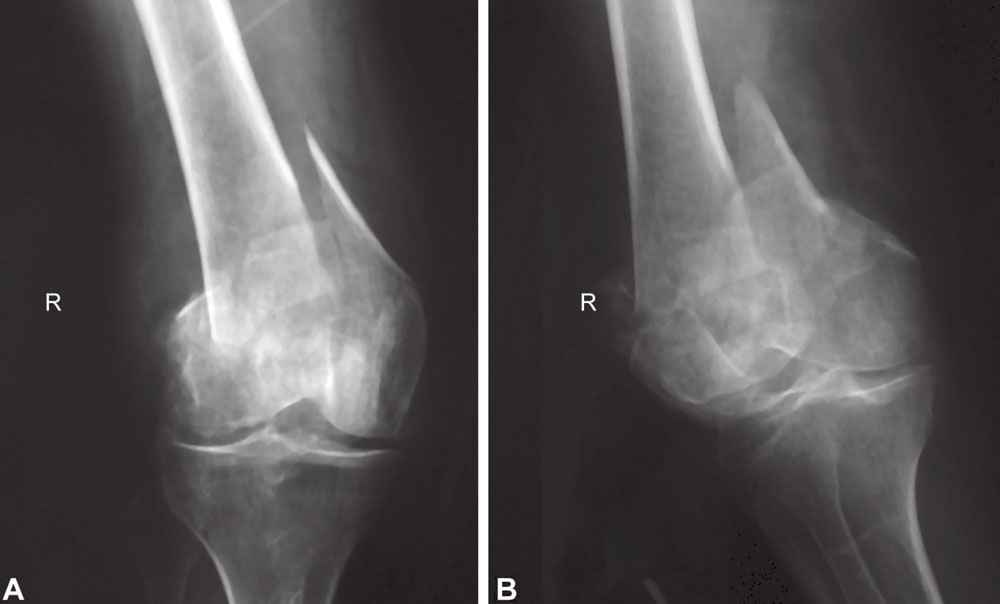

图A和图B受伤后前后位和侧位X线片显示左侧股骨远端关节内粉碎性骨折

一位79岁的妇女,由于在家中平地摔倒被送入医院。

图A和图B术后前后位和侧位X线片显示关节面平整,骨折力线良好

图A和图B患者在6个月时,感觉无疼痛且能进行良好的关节活动

最后,进行了远端股骨锁定钢板内固定。术后,X线片表现满意,感觉无疼痛且能进行良好的关节活动,得到了良好的功能恢复。